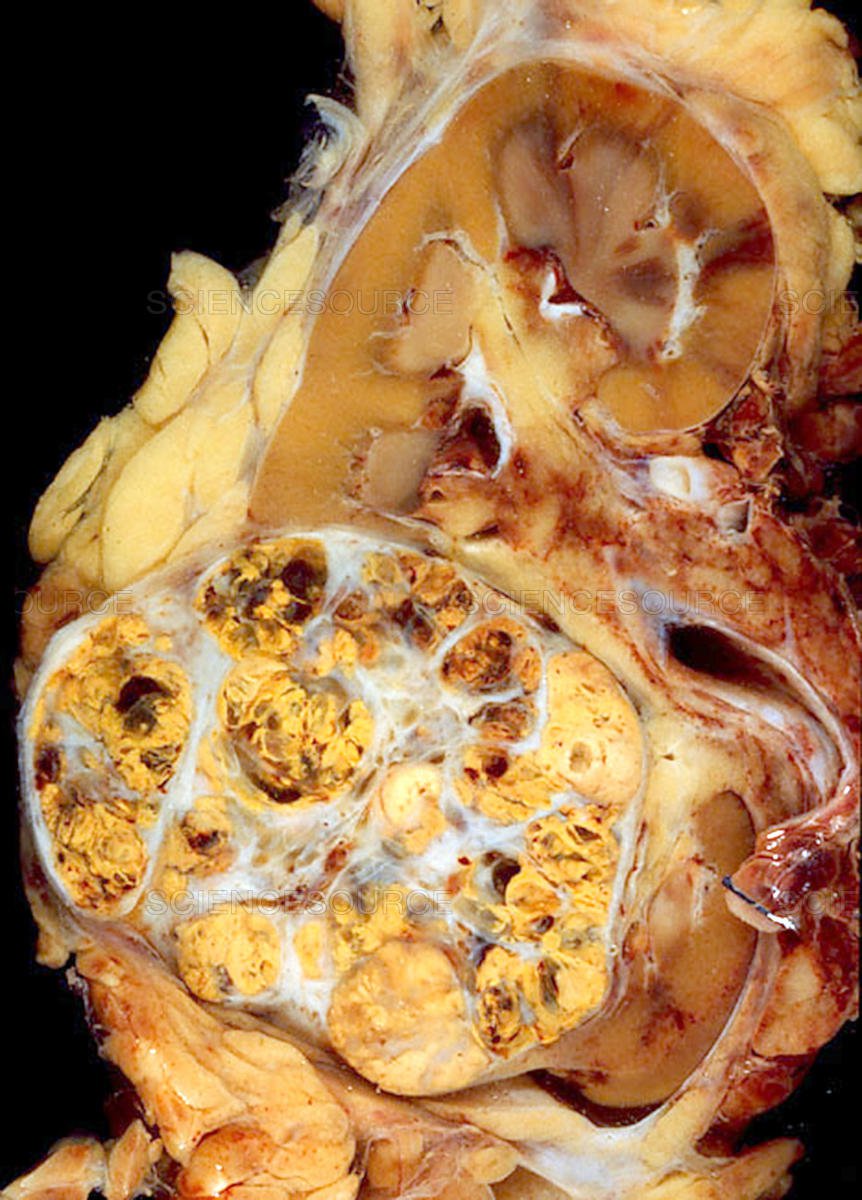

Ung thư thận là một loại ung thư ác tính phát triển từ các tế bào trong thận. Khối u ung thư thận có thể phát triển ra khỏi thận vào mô xung quanh và xâm lấn các tĩnh mạch, tuyến thượng thận hoặc các cơ quan lân cận.

Giải phẫu bệnh

Giải phẫu bệnh ung thư thận là một phương pháp điều trị thường được sử dụng để loại bỏ các khối u ác tính trong thận.Phẫu thuật ung thư thận thường được thực hiện dưới tình trạng gây mê đầy đủ và yêu cầu một bác sĩ phẫu thuật chuyên môn về ung thư thận. Có hai phương pháp chính để tiến hành phẫu thuật ung thư thận, đó là phẫu thuật mở và phẫu thuật tiểu phẫu.